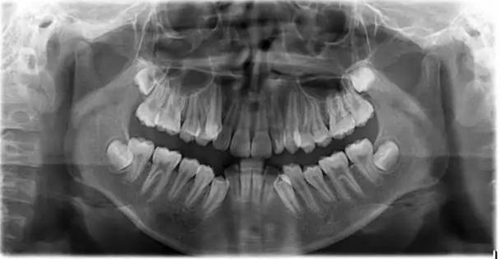

1500865770_445373.jpg1500865976_358577.jpg

此病例主要考慮的是擁擠度,磨牙及尖牙關(guān)系,前牙覆合覆蓋,生長(zhǎng)潛力和智齒。